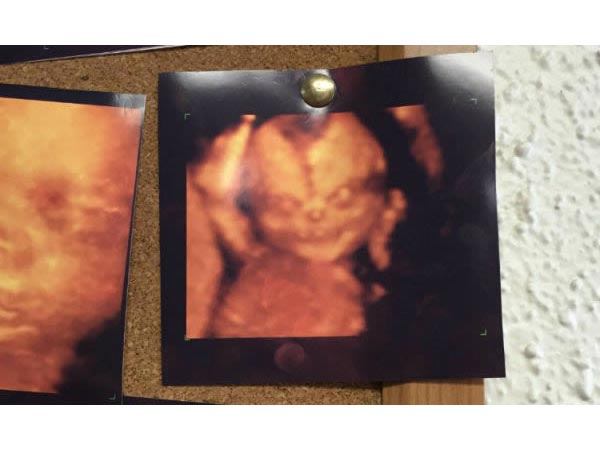

Eerie Resemblance To The Evil Emperor From Star Wars

The ultrasound of this unborn baby has a scary resemblance to the evil emperor from "Star Wars". The mother immediately spotted the cloaked figure staring back at her from a scan, and everyone in the scan room had a hearty laugh for this resemblance.